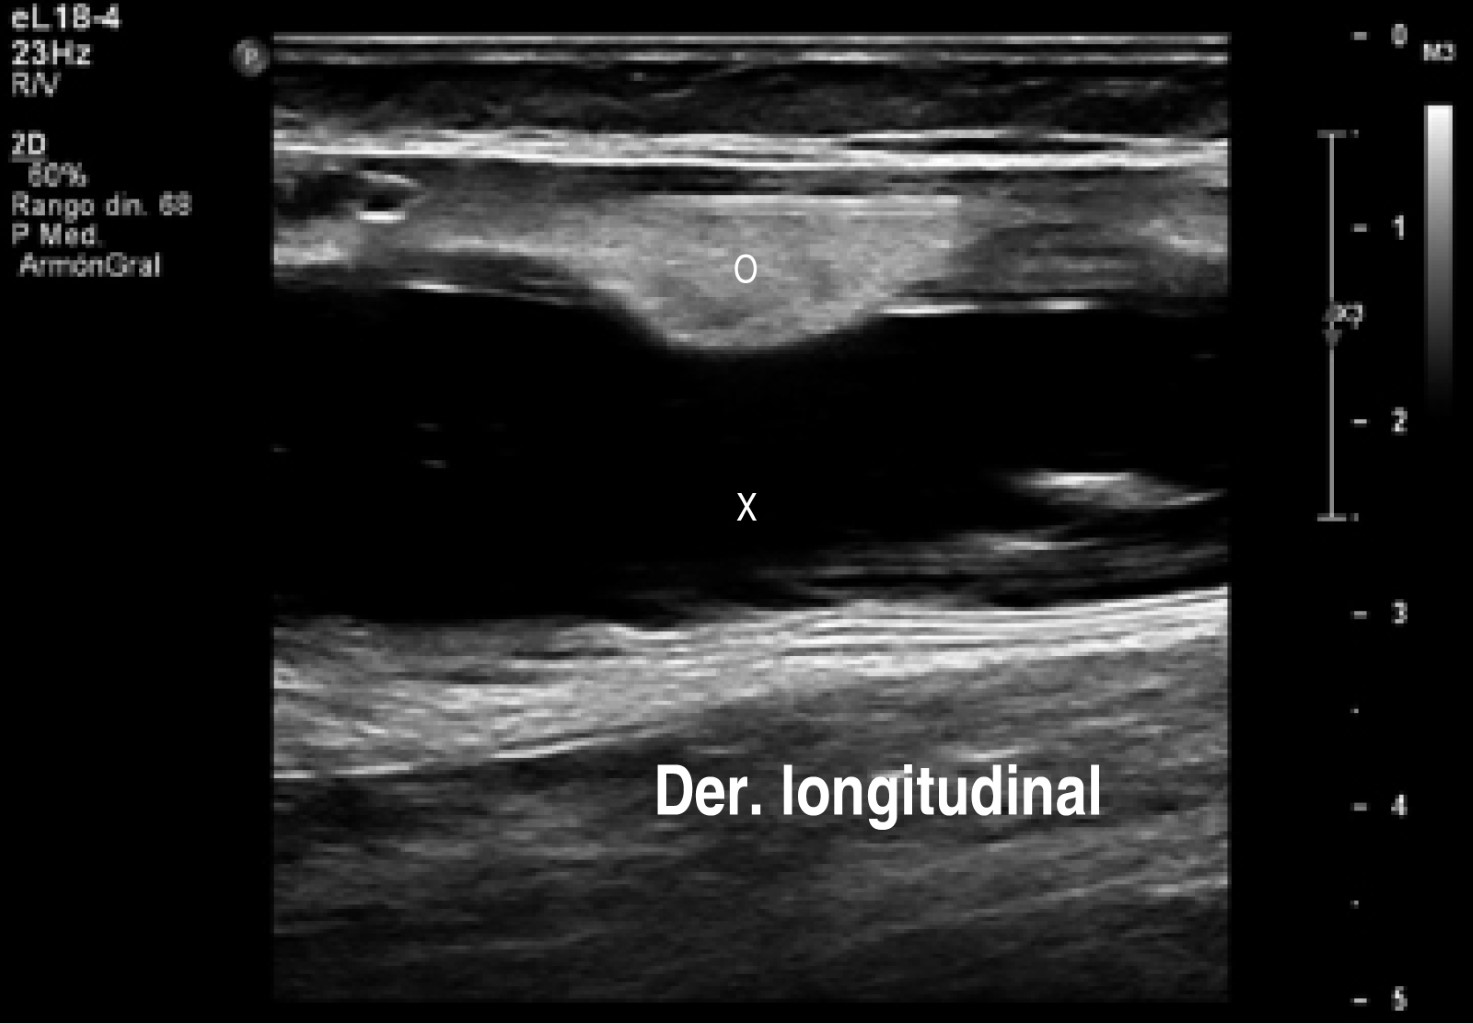

En el estudio de ultrasonido se encontró extensa colección líquida intracapsular de la pierna izquierda, sin descartar la ruptura del implante. El implante derecho con datos de ruptura y mínima colección.

Procedimiento quirúrgico (Figuras 1, 2, 3, 4 y 5):

El 24 de octubre se llevó a cabo el retiro del implante de la pantorrilla izquierda bajo anestesia local y sedación. El retiro del implante derecho se difiere para otro tiempo quirúrgico (dos meses) a petición de la paciente para que se facilitara su movilidad en el postoperatorio. En la imagen preoperatoria observamos el aumento de volumen de la pierna izquierda (Figura 6).